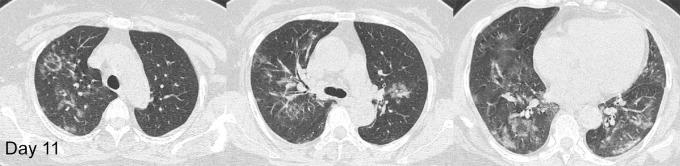

Longitudinal CT Findings in COVID-19 Pneumonia: Case Presenting Organizing Pneumonia Pattern.

Radiol Cardiothorac Imaging. 2020 Feb 14;2(1):e200031. doi: 10.1148/ryct.2020200031. eCollection 2020 Feb.